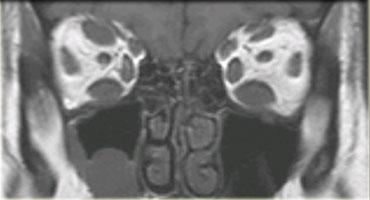

Hình bên trái là một ví dụ điển hình về bệnh cơ viêm có căn nguyên nội tiết: bệnh Graves, còn được gọi là bệnh mắt tuyến giáp.

Tình trạng viêm các cơ vận nhãn và mỡ hốc mắt kèm theo tăng thể tích dẫn đến lồi mắt.

Cùng bệnh nhân, ảnh chuỗi xung T2W mặt phẳng coronal.